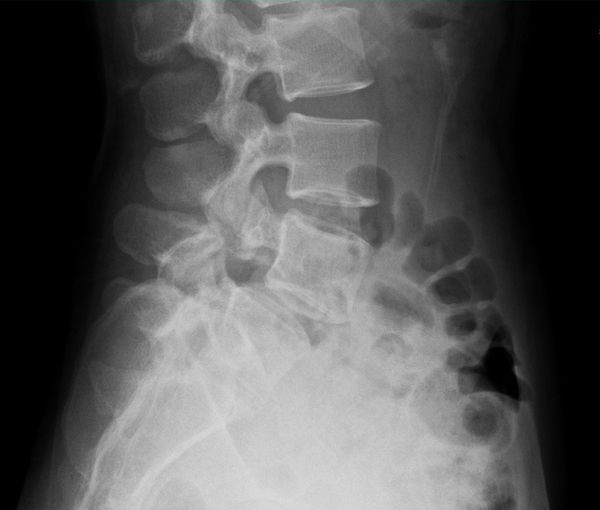

30歲出頭的女子剛開始重訓沒多久,在一次硬舉之後開始感到下背疼痛。原本以為春節假期休息一下就會好,沒想到疼痛一直持續。